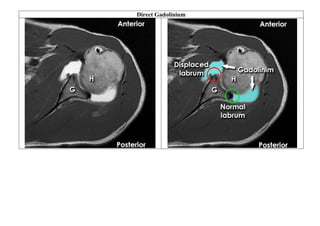

Contrast agents

The pre-gadolinium image shows only an indistinct area of

abnormality in the left cerebral hemisphere

The post-gadolinium image of the brain shows a very well-

defined area of enhancement – in this case due to a malignant

brain tumour

Pre and post-gadolinium T1-weighted images are compared in order to assess 'enhancement' of tissues.

Abnormal tissue, such as inflamed or cancerous tissue, is often more vascular than surrounding tissue and so 'enhances', appearing

brighter on post-gadolinium images

 Gadolinium is the most common contrast agent used for

MRI – it can be given intravenously or injected directly

into a body part

 Abnormal tissue may enhance more than surrounding

normal tissue following intravenous gadolinium

 Abnormal tissue may also retain gadolinium longer than

normal tissue

Direct Gadolinium